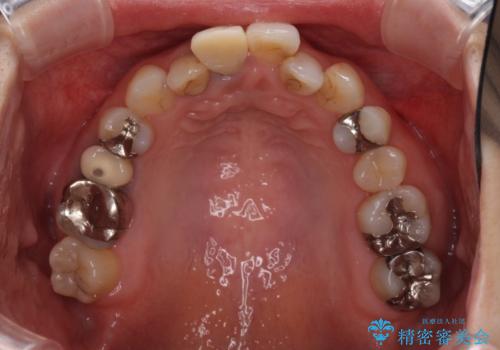

前歯のクロスバイトと治療が必要なむし歯 矯正とセラミックの総合歯科治療

前歯は根管治療が必要であったため、まずは根管治療を行いましたが、痛みが引いた後、矯正治療や前々から治療が必要と言われてきた歯を治療したいとのことでした。

前歯のクロスバイトはインビザラインで改善し、抜歯が必要な部分はインプラントを、その他むし歯が進行している歯はセラミッククラウンによる補綴治療することとしました。

仕事がお忙しく、インビザラインをあまりしっかりと使用できなかったようで、何とか長い期間をかけて歯列を整えることができました。

磨きにくく、何度もむし歯治療を繰り返していた前歯をスッキリと整えることができました。